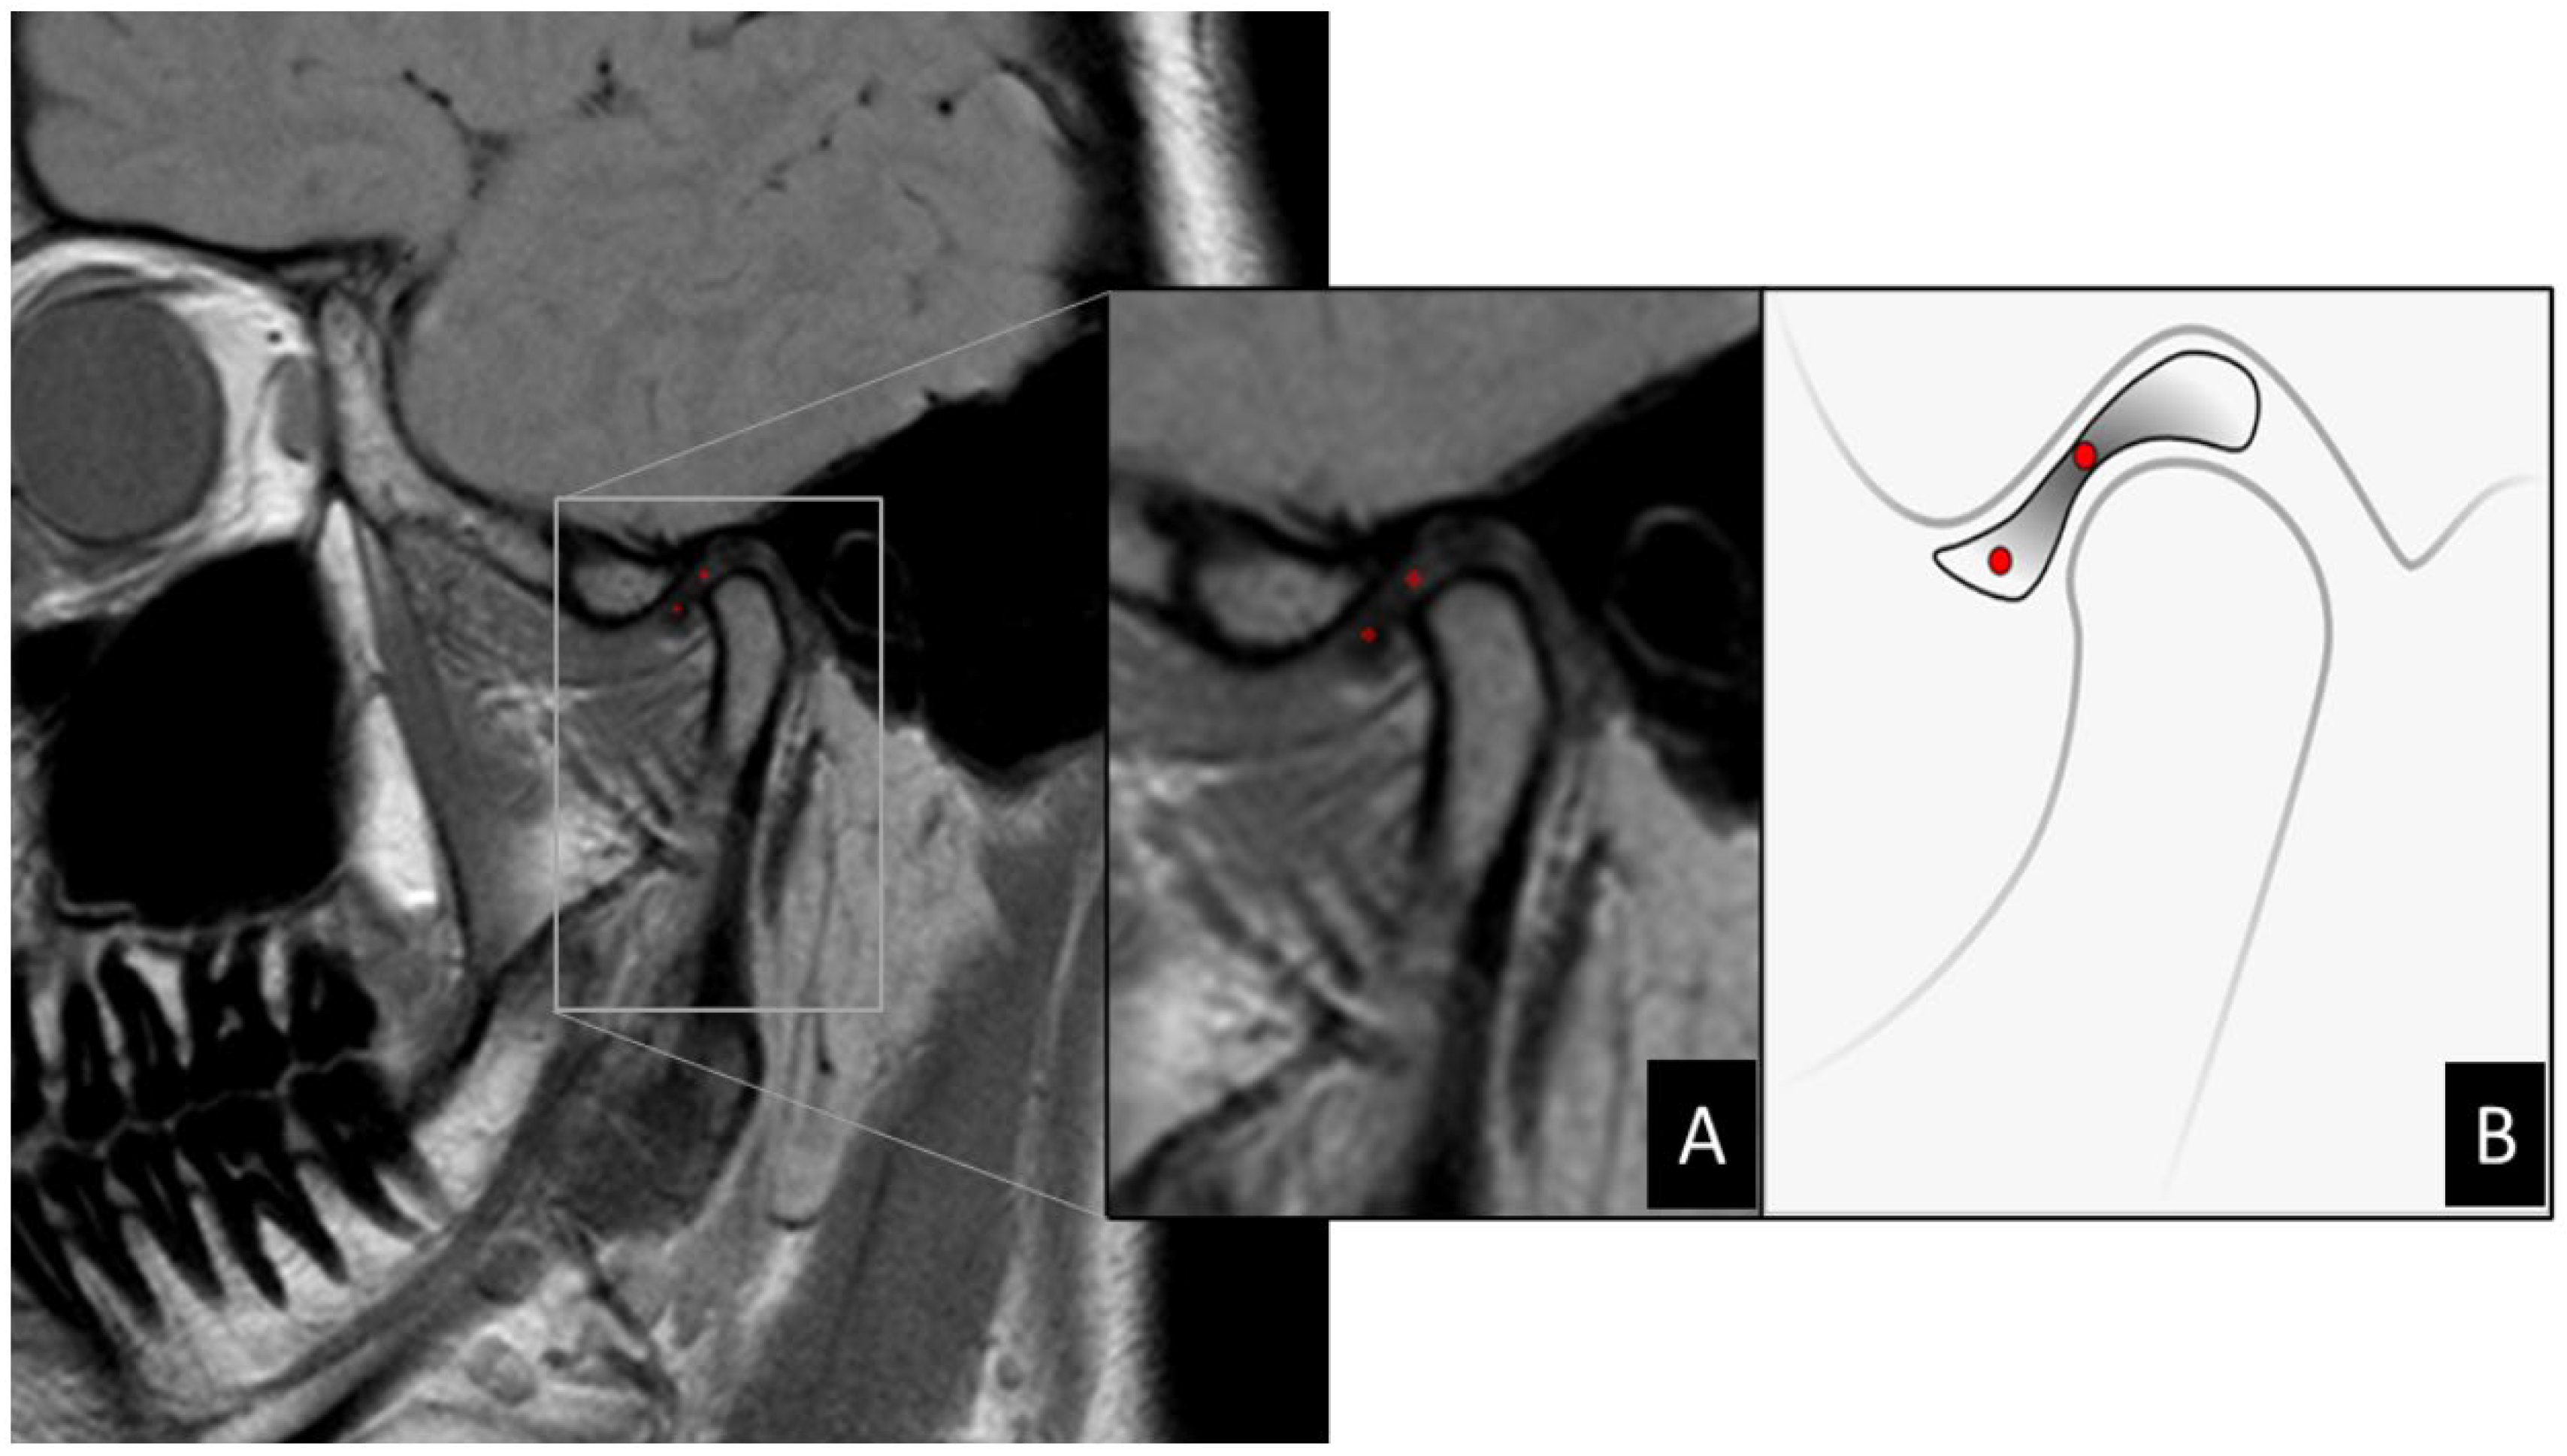

1. Introduction

2. Materials and Methods

2.2. MRI

2.3. Image Analysis

2.4. Image Processing